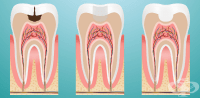

K02.4 Одонтоклазия

Одонтоклазия е нетипична форма на зъбен кариес. Това е състояние, характеризиращо се лезия, която пр...

K02.9 Зъбен кариес, неуточнен

Кариесът е често срещано заболяване в наше време. С редовни профилактични прегледи и правилна орална...

K03.3 Патологична резорбция на зъбите

Патологична резорбция на зъбите е процес, при който всички или част от зъбите са с нарушена структур...